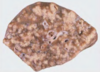

Condition

Pulmonary Adenocarcinoma